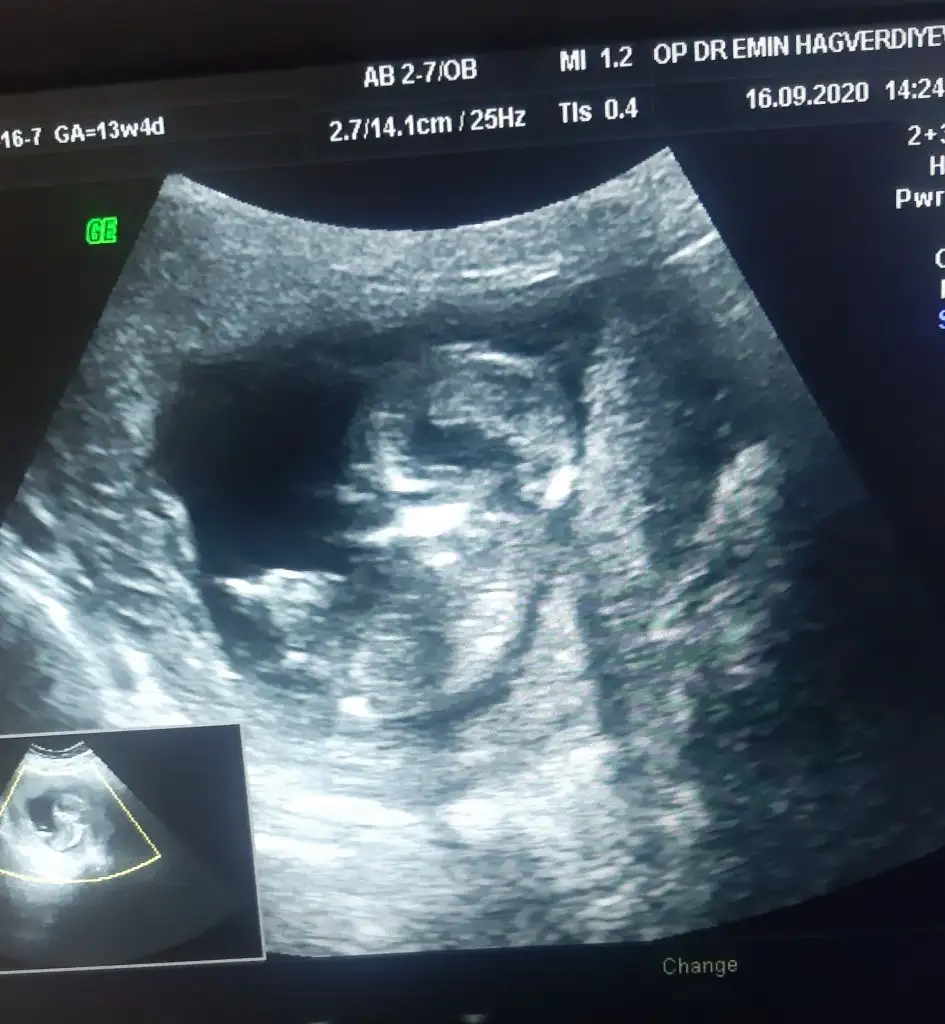

Diğer usgler belli değildi birdahami paylaştın cnm kaçırdım sanki 🙈 sağlıkla gelsin oglusun

Yok cnm ya hicbiri belirgin degildi arkadasta zaten ışıktan anladim nubdan degil yazmis seninle ilgisi yok yorumlarin için tesekkurler sen elinden geldigince yorum yaptıin🙂🙂oglusum olucsk ins nasipse 14+5 deyim . Bizimki cok yaramaz ya amuda kalkiyo ya cok hareket ediyor doktor ultrason goruntusude veremedi bayadir uygun pozisyonda olmadigi icin ben ekrani cektim.hep ..

Bu da pazartesi 14+2 de gittim bunu atmadum ama amuda kalkmis resmen Sipa 😅doktor bu sefer ben sormadan tekrar erkek dedi